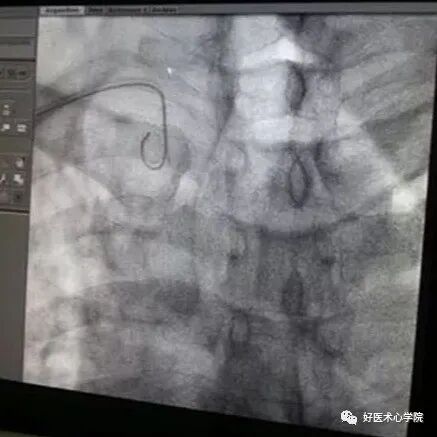

下降至窦底,使导丝盘成U型时,导管跟进,固定导丝,导管进入窦底。

造影导丝是什么珍藏 冠脉造影从流程到诊断,基础必备!_https://www.jmylbn.com_新闻资讯_第31张